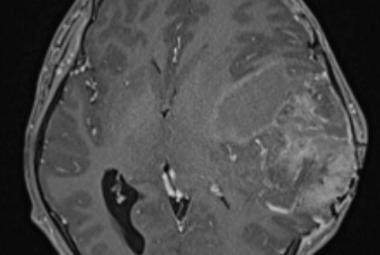

Temporal Ependymoma: A Case Study Emphasising Diagnostic Dilemmas and Therapeutic Challenges